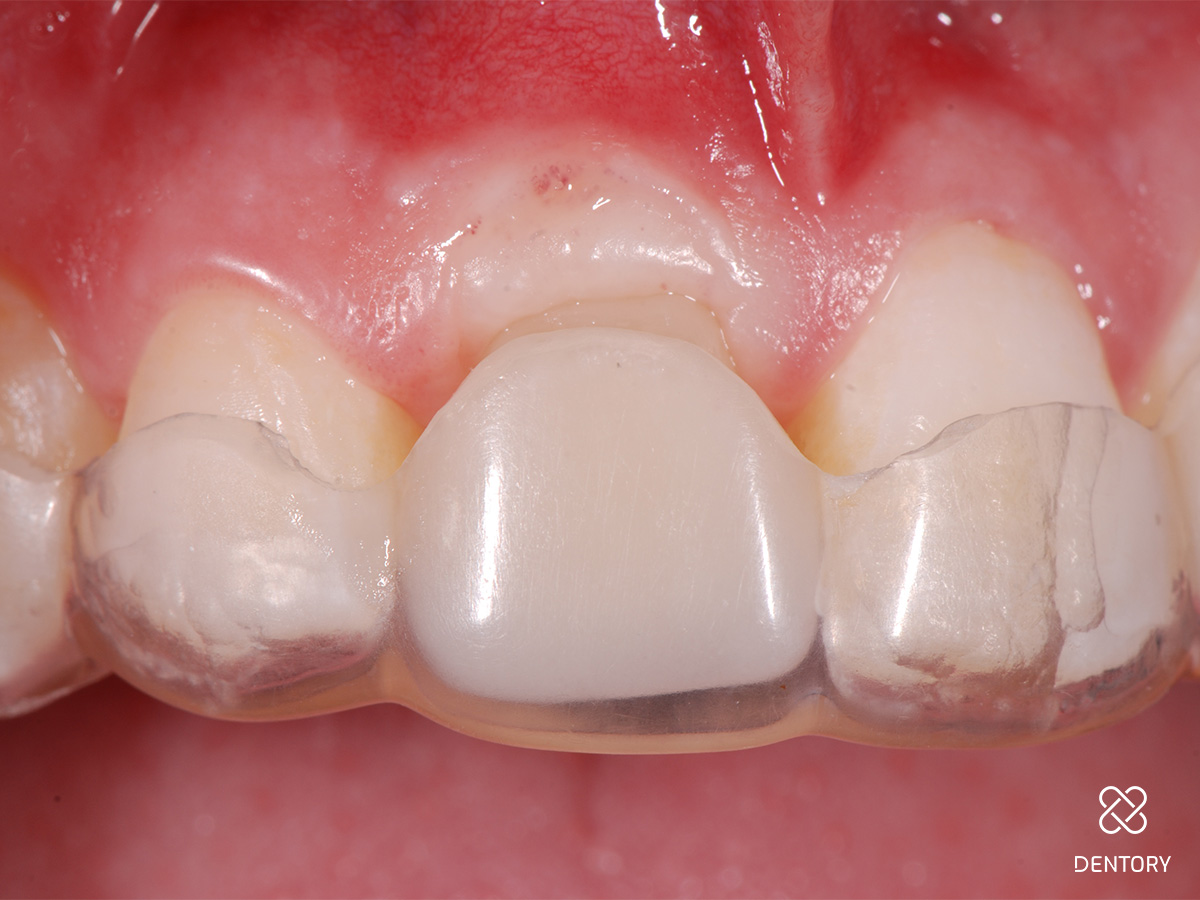

Abbildung 12

Provisorische Versorgung mit einer Tiefziehschiene; alternativ kann auch eine kleine Prothese oder eine Klebebrücke verwendet werden.